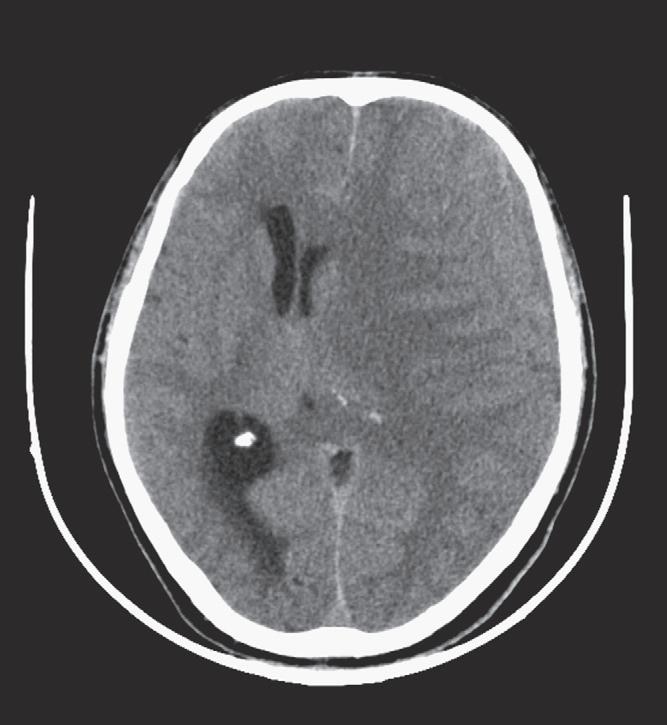

The appearance of ICH on a CT scan can vary depending on the age of the hemorrhage and the hemoglobin level. The attenuation of blood is typically based on the protein content, of which hemoglobin contributes a major portion. Therefore the appearance of hyperacute/acute blood is easily detected on a CT scan in patients with normal hemoglobin levels (approximately 15 g/dL) and typically appears as a hyperattenuating mass. This appearance is typical because, immediately after extravasation, clot formation occurs with a progressive increase in attenuation over 72 hours as a result of increased hemoglobin concentration and separation of low-density serum. On the other hand, in anemic patients with a hemoglobin level less than 10 g/dL, acute hemorrhage can appear isoattenuating to the brain and can make detection difficult. Subsequently, after breakdown and hemolysis, the attenuation of the clot decreases until it becomes nearly isoattenuating to cerebrospinal fluid (CSF) by approximately 2 months. In the emergency setting, one should be aware of the “swirl” sign with an unretracted clot that appears to be hypoattenuating and resembles a whirlpool; this sign may indicate active bleeding and typically occurs in a posttraumatic setting. It is important to recognize this sign, because prompt surgical evacuation may be required. The amount of mass effect on nearby tissues will depend on the size and location of the hemorrhage, as well as the amount of secondary vasogenic edema that develops.

Use of an intravenous contrast agent usually is not necessary for CT detection of ICH. If a contrast agent is used, an intraaxial hemorrhage can demonstrate an enhancing ring that is usually due to reactive changes and formation of a vascularized capsule, which typically occurs 5 to 7 days after the event and can last up to 6 months. Subacute and chronic extraaxial hematomas also can demonstrate peripheral enhancement, usually because of reactive changes and formation of granulation tissue. Unexpected areas of enhancement should raise concern, because active bleeding can appear as contrast pooling. Refer to the section on aneurysms and vascular malformations in this chapter for a discussion of CT angiography in the setting of acute ICH.

Intraventricular Hemorrhage

In the adult population, intraventricular hemorrhage (IVH) is typically caused by trauma. It can result from extension of a parenchymal hemorrhage into the ventricles or from redistribution of SAH. Primary IVH is uncommon and is usually caused by a ruptured aneurysm, an intraventricular tumor, vascular malformation, or coagulopathy (Fig. 1-8). Large IVHs are quite conspicuous on CT or MRI. They may occupy a majority of the ventricle(s) and may result in hydrocephalus and increased intracranial pressure. Small amounts of IVH may be difficult to detect; one must check carefully for dependent densities within the atria and occipital horns of the lateral ventricles. Normal choroid plexus calcifications in the atria of lateral ventricles, in the fourth ventricle, and extending through the foramina of Luschka should not be mistaken for acute IVH.